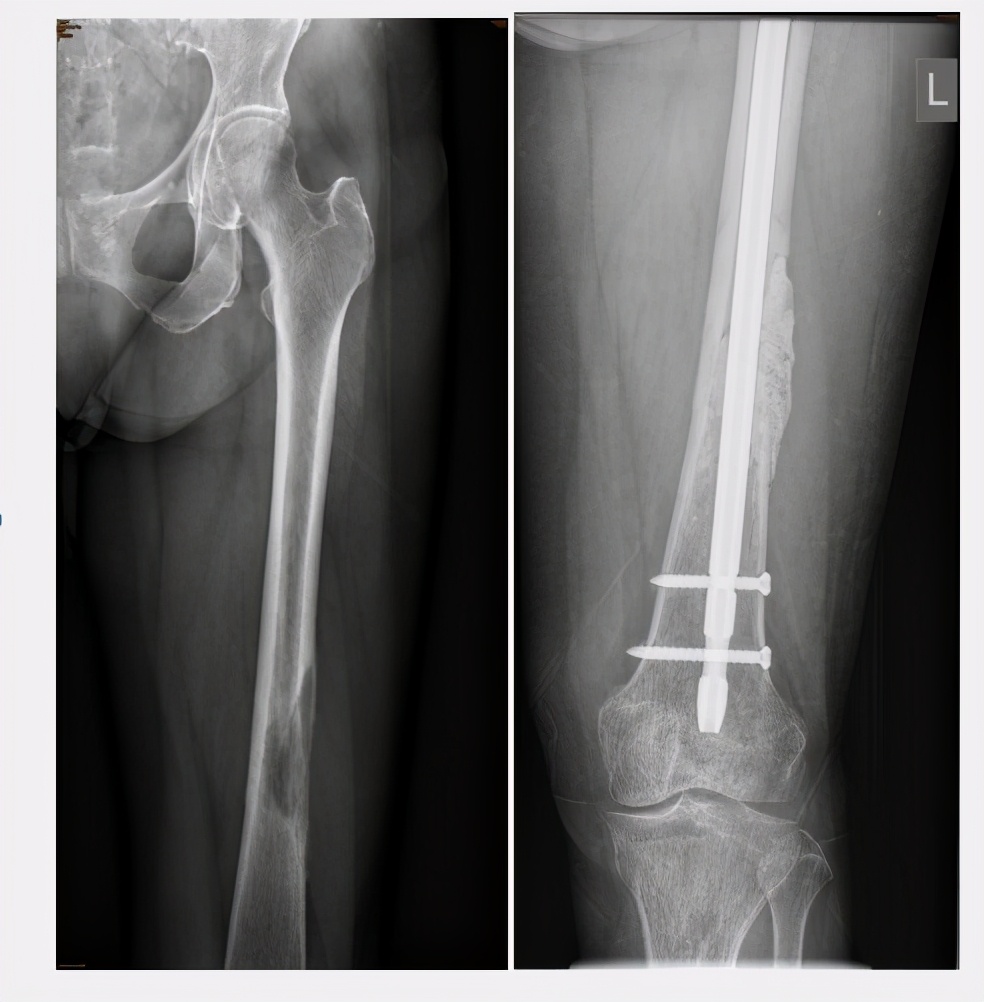

1.当癌细胞转移到四肢,病灶大于2.5厘米,病变破坏范围超过骨皮质50%,且患者出现完全性的骨质溶解时,可采取“肿瘤灭火+内固定、假体置换“的方法,对患者进行治疗。

外科手术治疗骨转移癌的目的有3个:一是缓解疼痛,保护肢体功能,提高患者的生活质量;二是治疗骨折、骨痛,并预防骨折的发生;三是切除骨的单发/寡转移,改善预后。